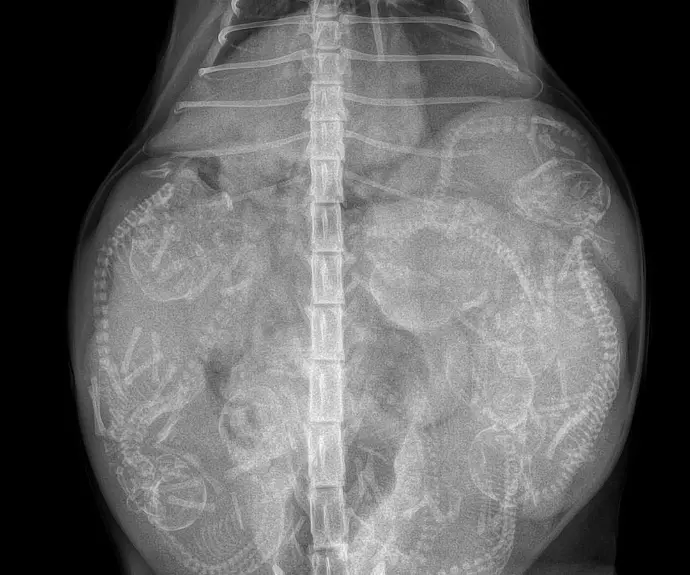

Nos femelles gestantes bénéficient d’un suivi régulier par échographie et/ou radiographie, et ne font pas plus d’une portée par an.